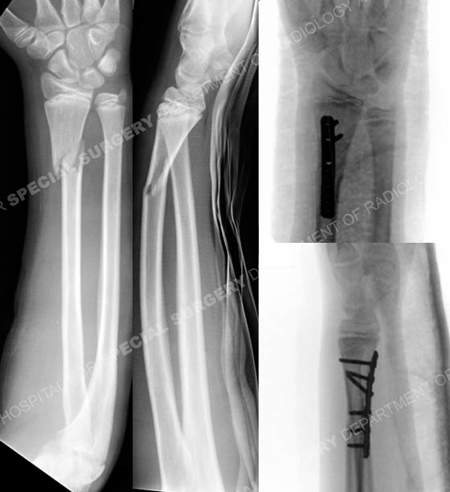

Anteroposterior and lateral radiographs (left images) revealing a right-sided distal radius fracture and associated dislocation of the distal radius ulna joint (Galeazzi fracture-dislocation) and intraoperative fluoroscopic radiographs (right images).